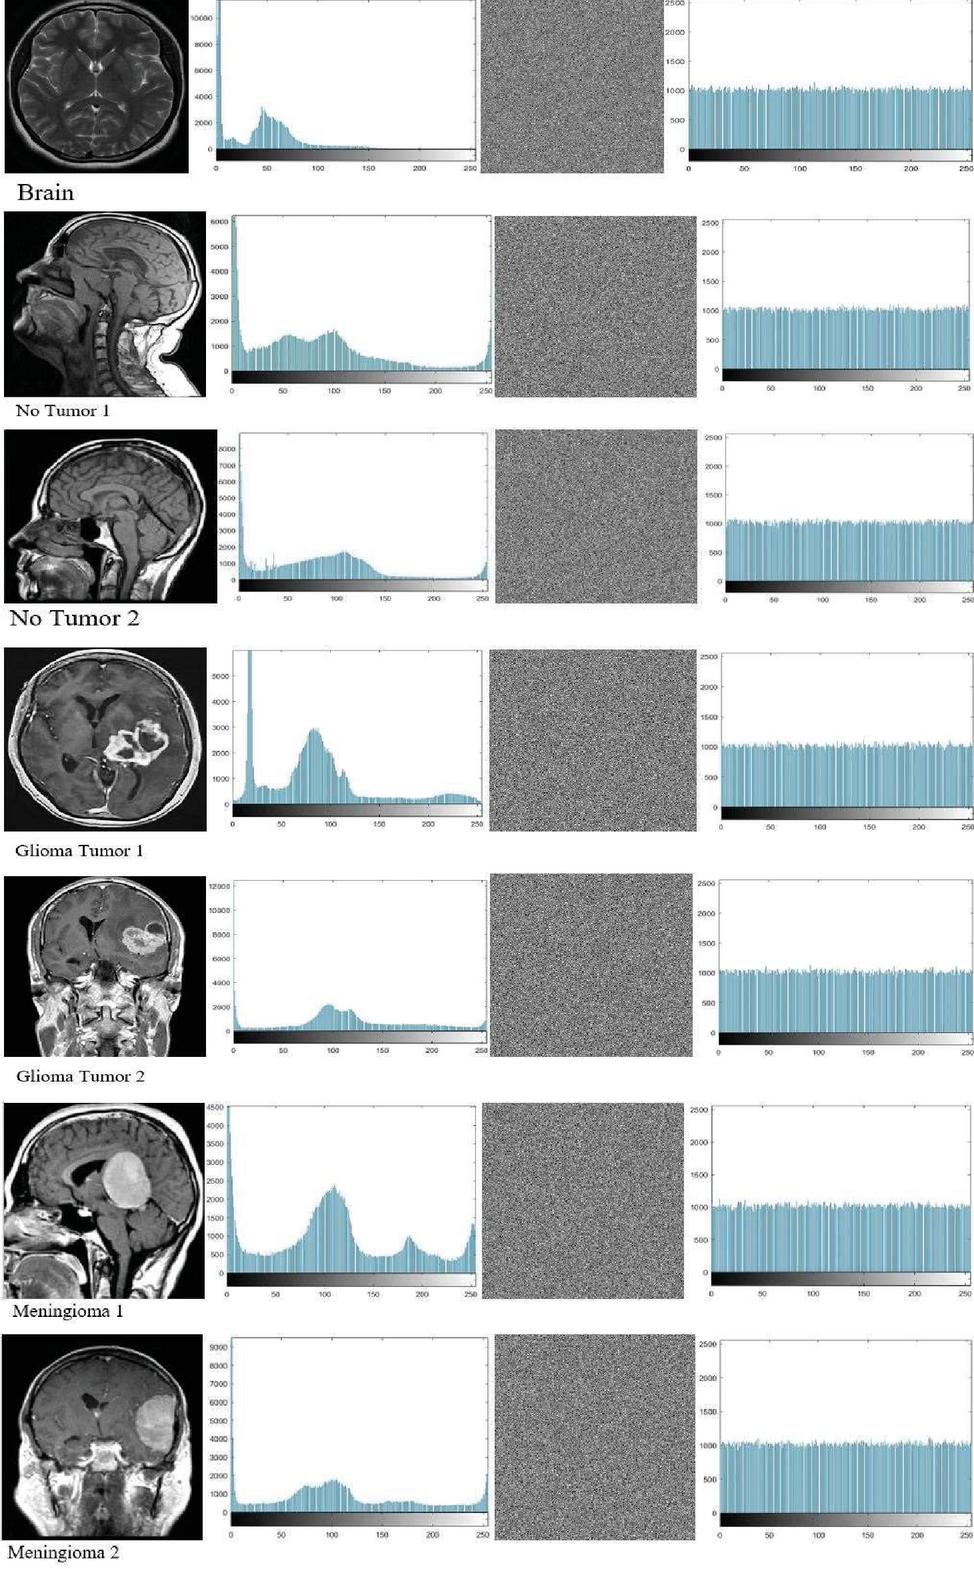

5.2 Histogram Analysis

A histogram is an analytical tool that represents grayscale levels on the horizontal axis and pixel density on the vertical axis to provide a comprehensive statistical description of an image’s content. Notably, histogram columns for encrypted images tend to have a uniform distribution to prevent attackers from discerning the encrypted content, as opposed to the different headers of histogram columns describing normal image content [19, 21, 24, 38, 39]. Figure 4 illustrates the effect of the proposed encryption algorithm on the test images, where the regularity of the graph columns of the encrypted images indicates the algorithm’s resistance to statistical attacks.

images

Figure 4 Histograms accompany both the unencrypted and encrypted images.